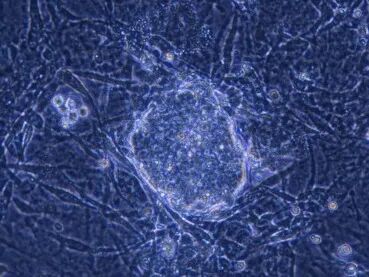

在显微镜下,研究人员观察到了一些形态与胚胎干细胞极为相似的细胞集落。起初,这些细胞甚至被怀疑是实验污染。然而随着实验的重复验证,研究团队逐渐确认这些细胞确实是通过基因诱导产生的。随后通过逐步剔除候选基因,研究者最终将关键因子缩减为四个转录因子:Oct3/4、Sox2、Klf4和c-Myc。这四个因子的组合能够将体细胞重新编程为具有多能性的细胞,即诱导多能干细胞。